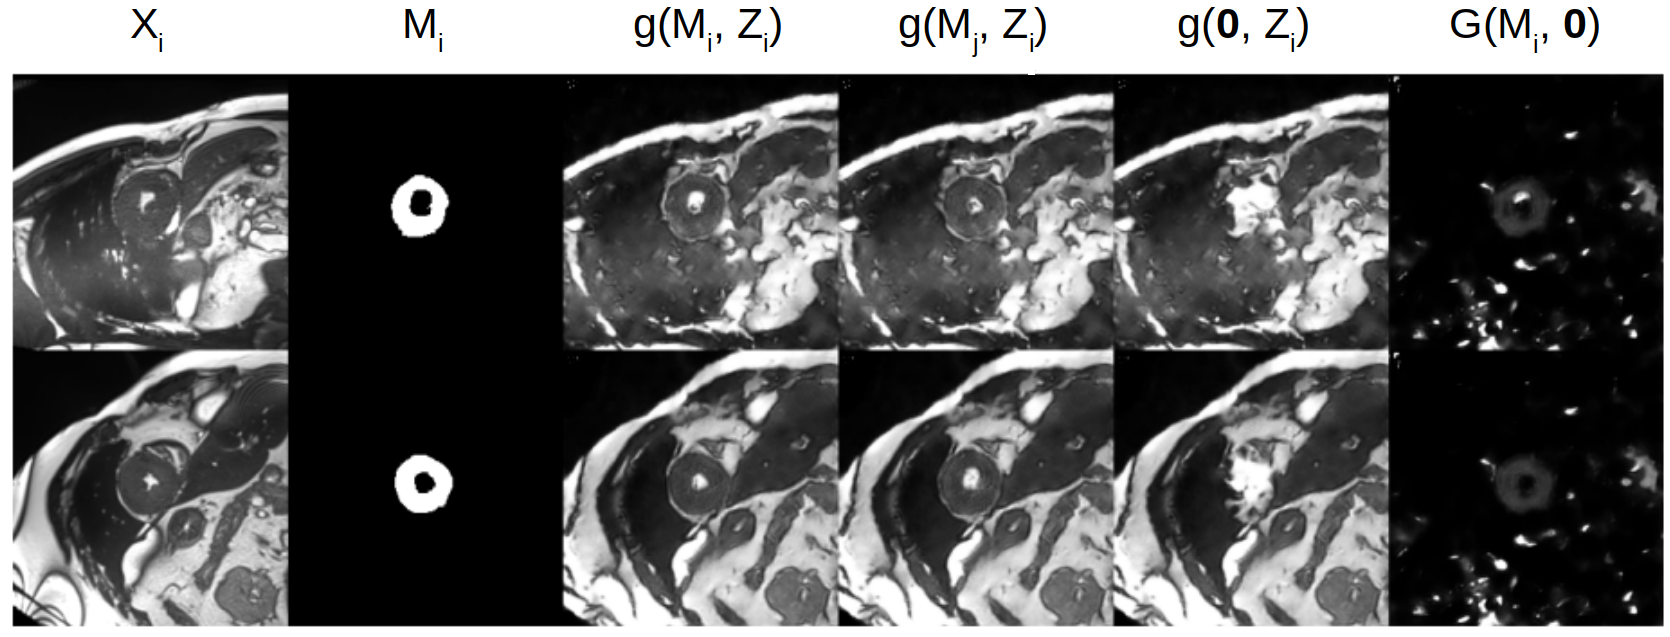

4.2 Latent space arithmetic

As a demonstration of our learned representation, in Fig. 3 we show reconstructions of input images from the training set using different combinations of masks and components. In the first three columns, we show the original input with the predicted mask and the input’s reconstruction. Next, we take the spatial representation from one image and combine it with the component of the other image, and vice versa. As shown in the figure (4th column) the intensities and the anatomy around the myocardium remains unchanged, but the myocardial shape and position, which are encoded in the mask, change to that of the second image. The final two columns show reconstructions using a null mask (i.e. ) and the correct in 5th column, or using the original mask with a in 6th column. In the first case, the produced image does not contain myocardium, whereas in the second case the image contains only myocardium and no other anatomical or MR characteristics.